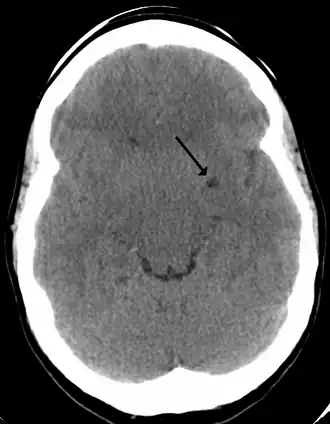

In humans, perivascular spaces surround arteries and veins can usually be seen as areas of dilatation on MRI images. While many normal brains will show a few dilated spaces, an increase in these spaces may correlate with the incidence of several neurodegenerative diseases, making the spaces a topic of research.[4]

Perivascular spaces are most commonly located in the basal ganglia and white matter of the cerebrum, and along the optic tract.[13] The ideal method used to visualize perivascular spaces is T2-weighted MRI. The MR images of other neurological disorders can be similar to those of the dilated spaces. These disorders are:[7]

Perivascular spaces are distinguished on an MRI by several key features. The spaces appear as distinct round or oval entities with a signal intensity visually equivalent to that of cerebrospinal fluid in the subarachnoid space.[7][14][15] In addition, a perivascular space has no mass effect and is located along the blood vessel around which it forms.[14]

The clinical significance of perivascular spaces comes primarily from their tendency to dilate. The importance of dilation is hypothesized to be based on changes in shape rather than size.[13] Enlarged spaces have been observed most commonly in the basal ganglia, specifically on the lenticulostriate arteries. They have also been observed along the paramedial mesencephalothalamic artery and the substantia nigra in the mesencephalon, the brain region below the insula, the dentate nucleus in the cerebellum, and the corpus callosum, as well as the brain region directly above it, the cingulate gyrus.[5] Upon the clinical application of MRI, it was shown in several studies that perivascular space dilation and lacunar strokes are the most commonly observed histological correlates of signaling abnormalities.[13]